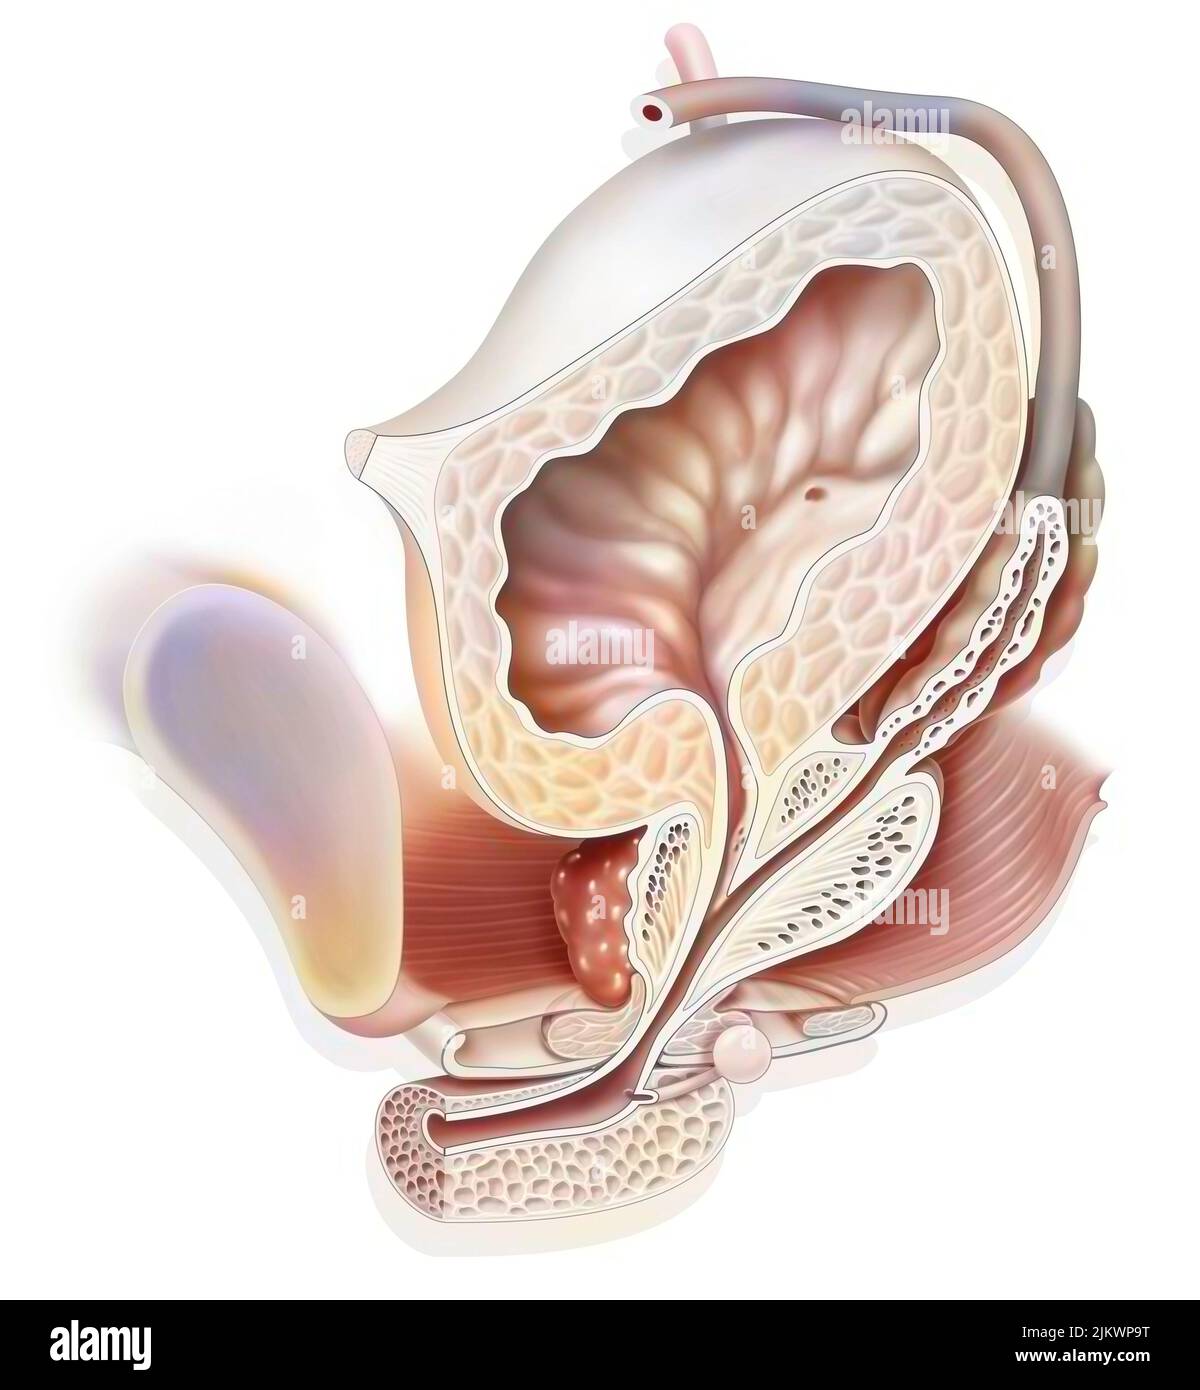

RF2PMGJB9–Männliche Fortpflanzungssysteme auf weißem Hintergrund. Vektordarstellung männlicher Fortpflanzungssysteme